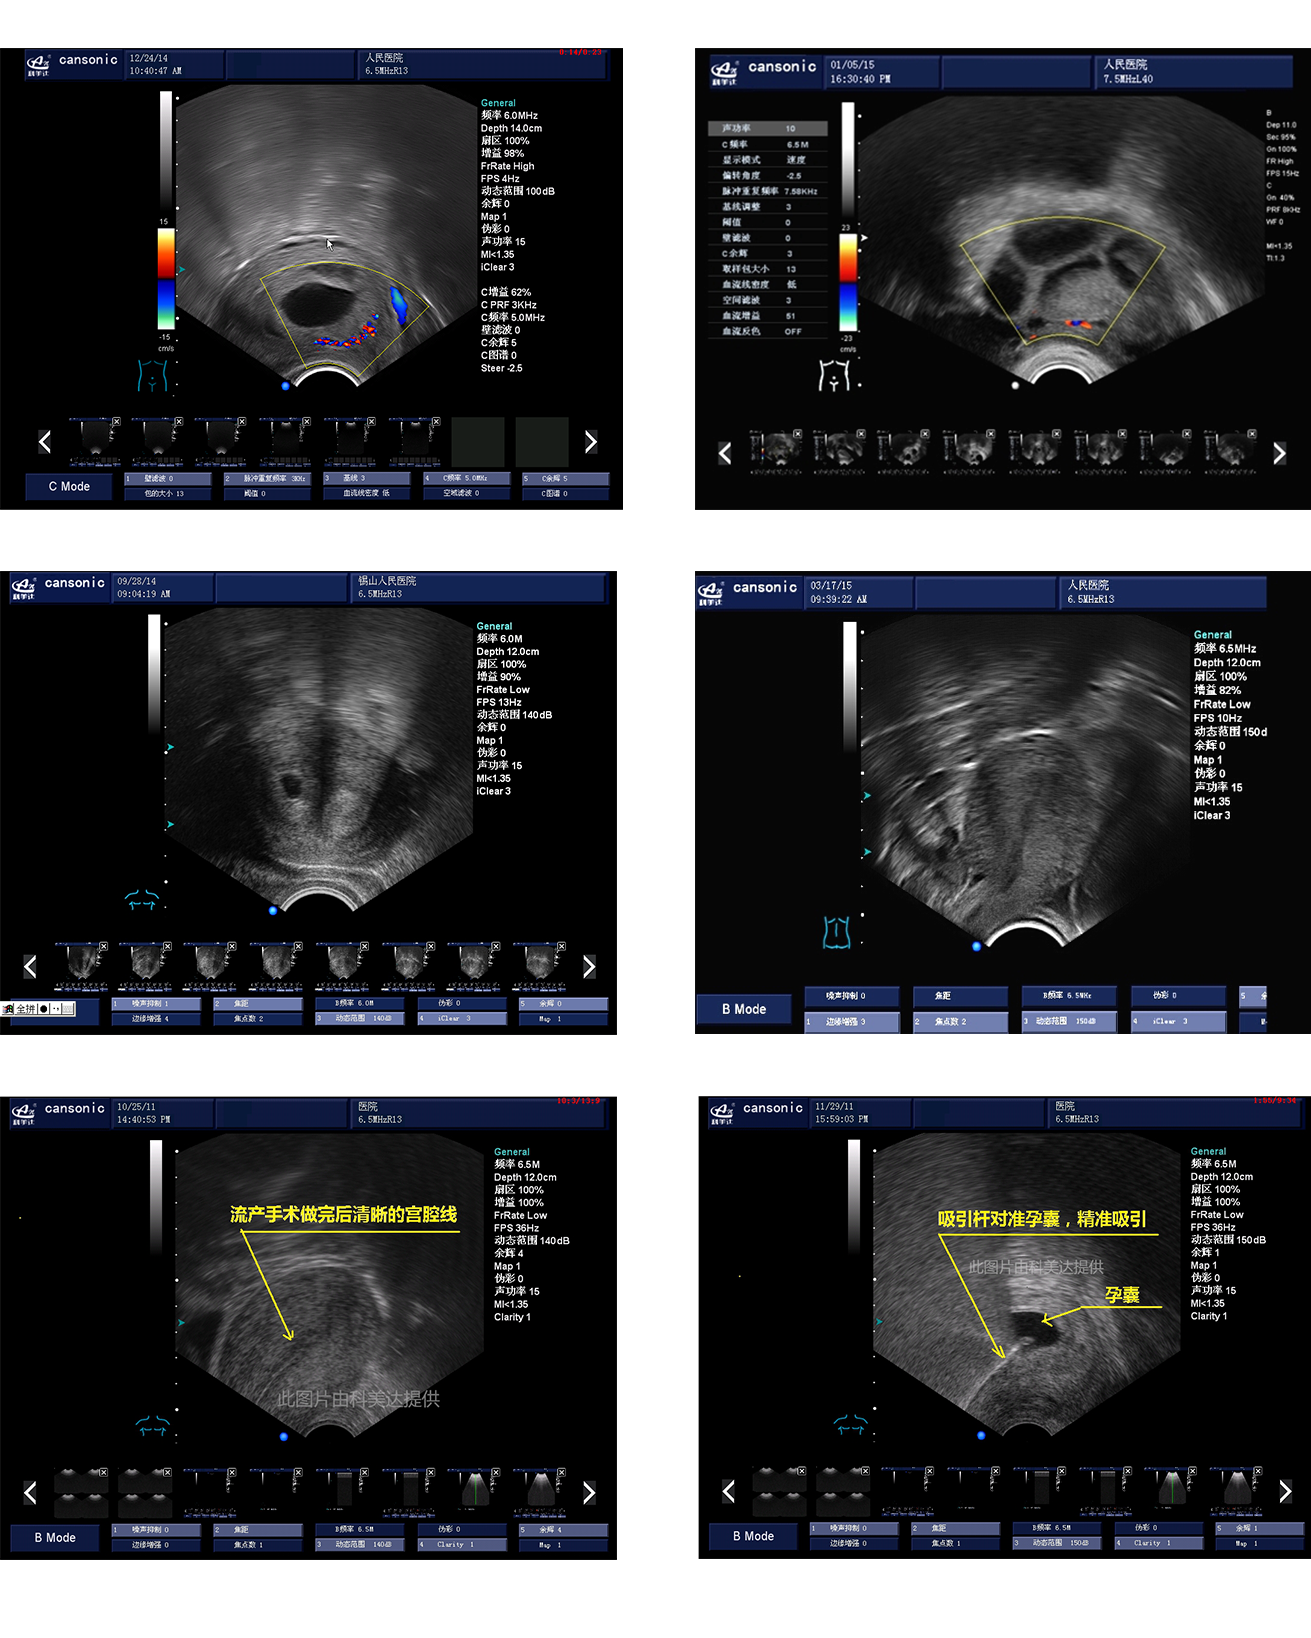

1、薈萃前沿彩超技術(shù),使得超聲監(jiān)測與手術(shù)操作完美融合,實現(xiàn)宮腔手術(shù)的全程監(jiān)測

2、復(fù)合成像技術(shù),增強組織回聲,減少回聲失落,得到清晰、真實的手術(shù)影像

3、血流靈敏度高,清晰可見

臨床圖示